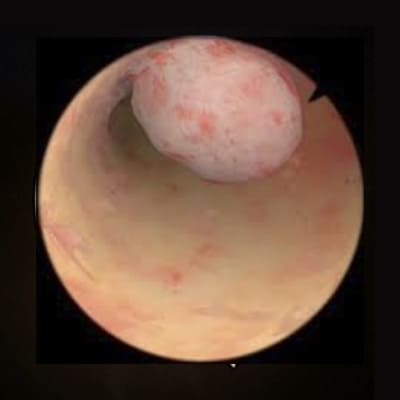

Pólipo endometrial